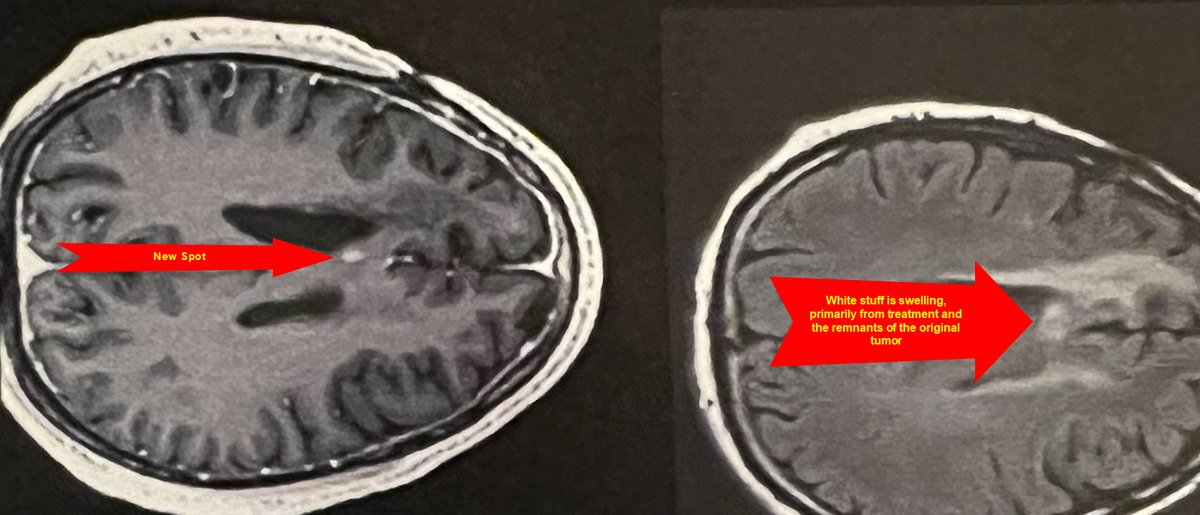

This feed will sortof document my journey with glioblastoma

/1 We are in the grind it out phase of this battle,finished chemo week last week with the normal fatigue and nausea, which lingers and even grows into the following (this) week. Wed. the following week things get better so today looks good- especially because @MariaGreen628 and I